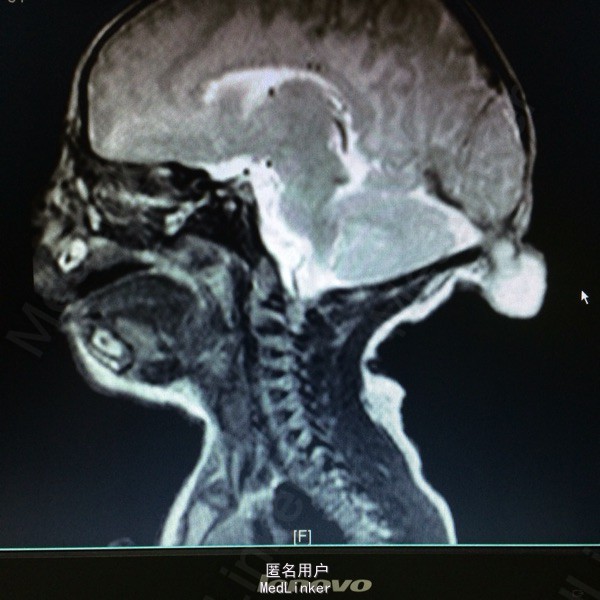

主诉:发现枕部包块1月余 病史:患儿2月大,第3胎第3产,经剖宫产,查体发现枕后部有一圆形肿物突出,约等3*3大小,透光实验阳性,质软。

查体:神志清醒,枕后部可见一圆形肿物突出,约3*3cm大小。质软,表面无溃疡等 辅助检查:胸片提示新生儿羊水吸入综合症,头颅MR提示局部脑脊膜膨出

诊断:后枕部脑脊膜膨出 处理:行脑脊膜膨出修补术,病理提示符合脑脊膜膨出